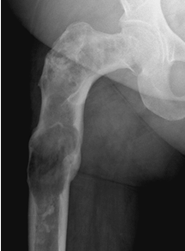

Fig 104. Displasia fibrosa.

Rx AP. Deformidad en cayado de pastor, secundaria a displasia fibrosa.